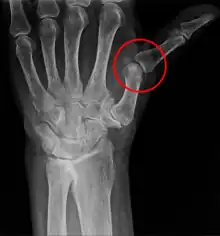

A subluxation is an incomplete or partial dislocation of a joint or organ.[1]

According to the World Health Organization (WHO), a subluxation is a "significant structural displacement", and is therefore always visible on static imaging studies, such as X-rays.[2][3][4]

A subluxation of a joint is where a connecting bone is partially out of the joint.[12] In contrast to a luxation, which is a complete separation of the joints, a subluxation often returns to its normal position without additional help from a health professional.[13] An example of a joint subluxation is a nursemaid's elbow, which is the subluxation of the head of the radius from the annular ligament. Other joints that are prone to subluxations are the shoulders, fingers, kneecaps, ribs, wrists, ankles, and hips affected by hip dysplasia. A spinal subluxation is visible on X-rays and can sometimes impinge on spinal nerve roots, causing symptoms in the areas served by those roots. In the spine, such a displacement may be caused by a fracture, spondylolisthesis, rheumatoid arthritis,[14] severe osteoarthritis, falls, accidents and other traumas. This is common in Ehlers–Danlos Syndrome.[15]